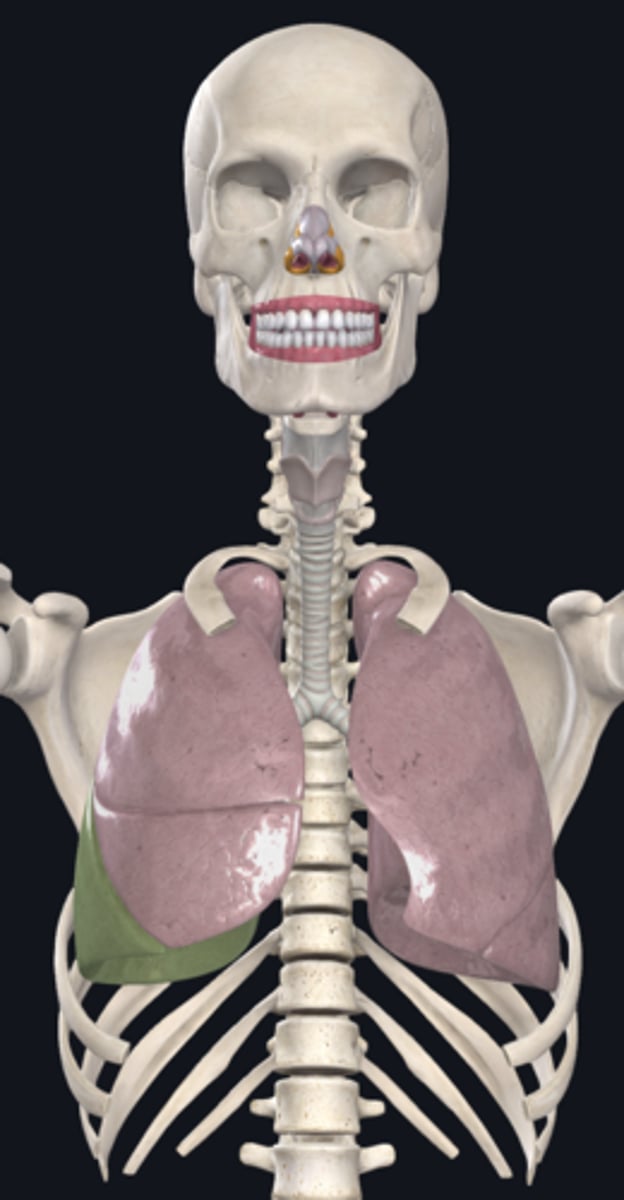

right lung

superior lobe of right lung

middle lobe of right lung

inferior lobe of right lung

left lung

superior lobe of left lung

inferior lobe of left lung

base (diaphragmatic surface)

apex

pulmonary artery

pulmonary vein

hilum of right lung

hilum of left lung

diaphragm